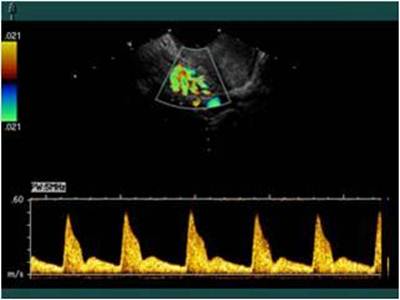

Помимо КТГ, в диагностике гипоксии плода во время беременности важное значение имеет допплерометрической оценке кровотока в системе мать-плацента-плод. Наиболее ценная информация о состоянии фетоплацентарного комплекса может быть получена при одновременном исследовании кровотока в обеих маточных артериях, артериях пуповины, во внутренних сонных или магистральных артериях головного мозга.

Допплерометрия в системе мать-плацента-плод (норма).О нарушении маточно-плацентарного кровообращения свидетельствует уменьшение диастолического кровотока в маточных артериях, о нарушении фетоплацентарного – снижение диастолического кровотока в артериях пуповины, нулевое или отрицательное их значение